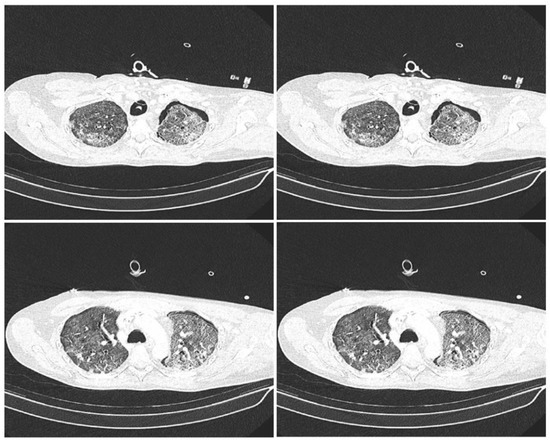

2. Materials and Methods

2.2. Methods